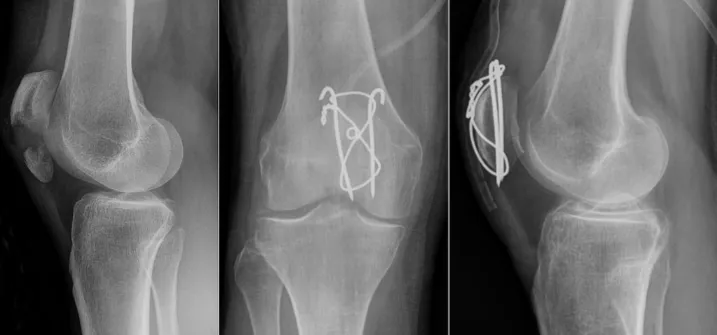

髕骨骨折 手術有哪些?

髕骨骨折 手術的方式會因患者的情況、骨折部位和骨折程度等因素而有所不同,一般有以下幾種手術方式:

開放性手術:器械將骨頭復位並使用螺釘、鋼板、釘子等固定器材將骨頭固定在正確的位置。

關節鏡下手術:通過小切口和關節鏡器械將骨頭復位,使用細小的固定器材進行內固定。

開放性復位外固定手術:使用鋼釘或針對骨骼的外固定器件,將骨頭復位並固定。